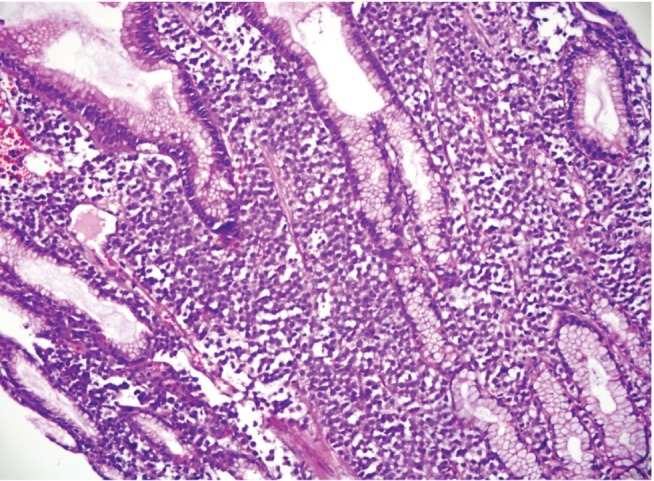

Figure 3

Immunostained section shows diffuse and strong reactivity for CD38 (×200).